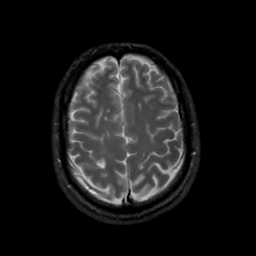

MR Study #20 October 6, 1991 -- Slice #39

[Home][Help][Clinical][Tour 1][Tour 2] Slice 39